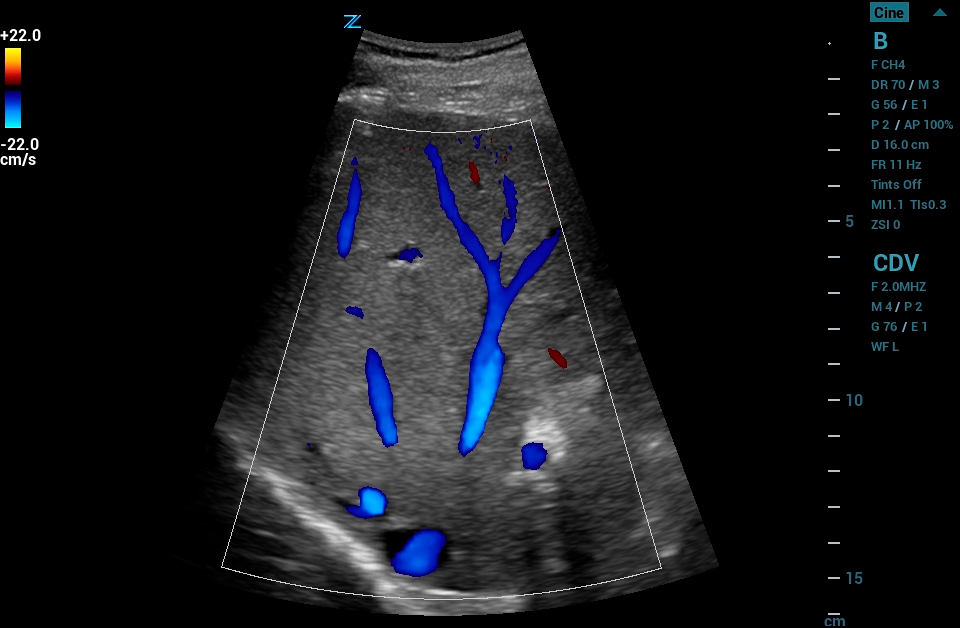

CEUS

Contrast Enhanced Ultrasound (CEUS), Mindray’s unique approach to contrast imaging, allows clinicians to obtain the information needed with a lower dose of the contrast agent. CEUS is now available on all imaging transducers (1-20MHz).